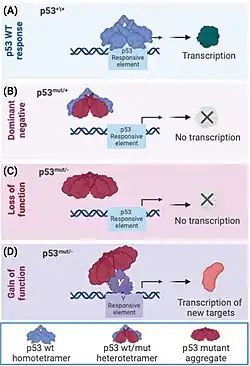

Most cancer-associated mutations in TP53 occur in the DBD, impairing DNA binding and transcriptional activation. These are typically recessive loss-of-function mutations. By contrast, mutations in the OD can exert dominant negative effects by forming inactive complexes with wild-type p53.

Diagnostic and prognostic significance

This image shows different patterns of p53 expression in endometrial cancers on chromogenic immunohistochemistry, whereof all except wild-type are variably termed abnormal/aberrant/mutation-type and are strongly predictive of an underlying TP53 mutation:[92]